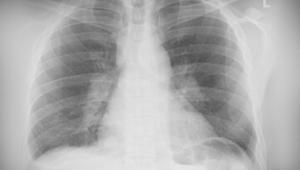

Pulmonary LAM can be diagnosed using high-resolution CT imaging, which will typically show round, thin-walled cysts throughout the lungs, together with some features of TSC.1,2